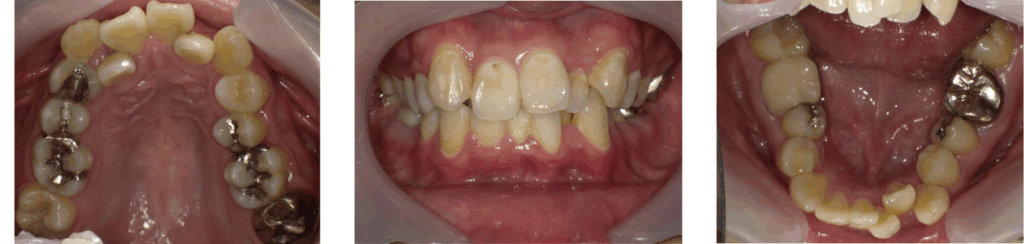

40代男性:マウスピースで仕事を続けながら自然な口元に

ここでは、当院でマウスピースを用いた矯正治療を行った症例をご紹介します。仕事を続けながら、目立たない装置で自然な口元を目指したケースです。

| 年齢 | 48歳 |

| 性別 | 男性 |

| 治療の理由(主訴) | 以前からガタガタの歯並びが気になっていたが、期間や費用もかかるので、諦めかけていた。 |

| 治療の背中を押したきっかけ | 50歳を目前として、自分の体の健康に目を向け自己投資をしようと思った。 |

| 周囲の反応 | 矯正治療前は自分の子供に「パパ、変な歯が生えてるー!」とバカにされていたが、きれいに歯が並んでびっくりしていた。 |

| 治療方法 | マウスピース矯正(インビザライン) |

| 治療期間 | 2年1か月 |

| 費用 | 88万円 |

| 生活背景 | 人前で話をすることが多い仕事のため、目立たないマウスピース矯正を希望。 |

| 年齢特有の対応 | ガタガタがかなり重度だったため、上下で合計3本の歯を抜歯する効率を考えた矯正治療プランを立てた。 |

治療前